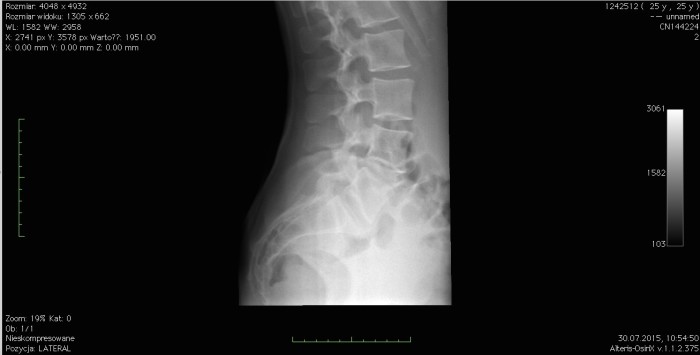

Kiedy przydatne jest wykonanie zdjęcia rentgenowskiego (RTG)?

Potoczny rentgen to podstawowe badanie dodatkowe w ortopedii, choć jego możliwości są przez pacjentów bardzo często przeceniane. Diagnostykę RTG stosuje się głównie w celu wykluczenia urazów tkanki kostnej, ponieważ praktycznie tylko kości są na tego rodzaju zdjęciach widoczne. Rentgen absolutnie nie nadaje się do oceny tkanek miękkich typu urazy więzadeł, mięśni czy otaczające je struktury nie będących elementami kostnymi.

Dlaczego właśnie to badanie wykonuje się najczęściej? Ponieważ niewykryte złamanie lub pęknięcie kości jest bardzo groźne i może prowadzić do bardzo nieprzyjemnych konsekwencji w postaci zagrożenia trwałej utraty zdrowia, a nawet życia. Wykonanie rentgena nie daje gwarancji, iż inne tkanki nie są uszkodzone, jednak daje względną pewność, że uraz nie jest na tyle poważny, iż konieczna jest natychmiastowa interwencja chirurgiczna lub pobyt w szpitalu.

Zdjęcie rentgenowskie jest przydatne głównie do oceny uszkodzeń i patologii tkanki kostnej.